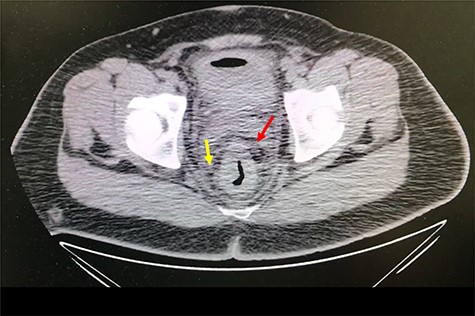

A 32-year-old man with no past medical or surgical history presented to the emergency department (ED) in April 2018, distressed and complaining of worsening pneumaturia for the past 3 days. The patient reported a 2-week history of polyuria, dysuria, suprapubic pain, tenesmus and inability to control his sphincters, prior to the ED-onset presentation. Further history revealed a 50-pound involuntary weight loss in a 5-month period, with partially treated urinary tract infections without resolution. He denied toxic habits, high-risk sexual behavior nor family history for colorectal cancer or inflammatory bowel disease. Based on the symptoms described, the rare triad of Gouverneur’s syndrome related to the EVF was considered. Physical evaluation revealed no palpable anorectal masses, adequate rectal tone and no visible gross blood. Urine analysis showed pyuria, hematuria, proteinuria with urine culture positive for Escherichia coli. Abdominopelvic computed tomography (CT) scan showed circumferential wall thickening of the rectum with surrounding fat stranding and numerous prominent pelvic lymph nodes (Fig. 1). Additionally, the scan showed pericolonic gas and fluid collection with a fistulous tract adjacent to the proximal rectum and the bladder (Fig. 2). In Figure 3, two hepatic hypodense lesions located in the right lobe of the liver were identified suggestive of metastasis. During colonoscopy, at approximately 20 cm from the anal verge a large, firm, irregular, friable, concentric mass was identified obstructing 95% of the lumen (Fig. 4). During surgery, the mass was not amenable for resection, due to its low pelvic location and size; a loop colostomy was performed for decompression, with liver tru-cut needle biopsy. Intraoperative cystoscopy was unsuccessful in placement of ureteral stents due to tumor invasion to the bladder.

Axial abdomen and pelvis CT scan showing hepatic hypodense lesion and possible liver metastasis (yellow arrow).